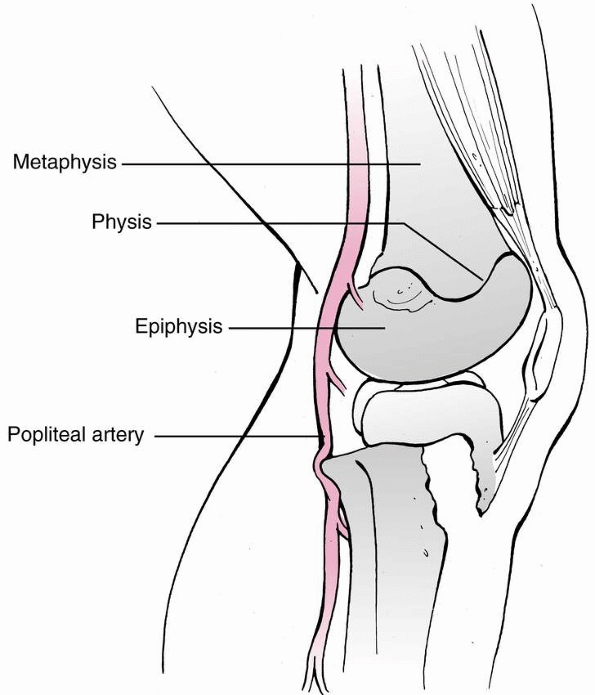

surface of the distal femur by only a thin layer of fat. Directly

overlying muscles. As the popliteal artery continues distally, it lies

on the posterior capsule of the knee joint between the femoral

condyles. At this level, the middle geniculate artery branches

anteriorly to enter the posterior aspect of the distal femoral

epiphysis. The popliteal artery and its branches are vulnerable to

injury from the distal femoral metaphysis at the time of hyperextension

injury.